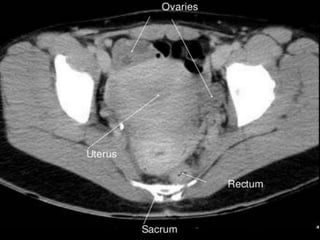

Urinary Bladder:

 The urinary bladder is covered superiorly by peritoneum.

 The body is a hollow muscular cavity.

 The neck is continuous with the urethra.

 The trigone is a smooth triangular area of mucosa located

internally at the base of the bladder.

 The base of the triangle is superior and bounded by the two

openings of the ureters.

 The apex of the trigone points inferiorly and is the opening for

the urethra.